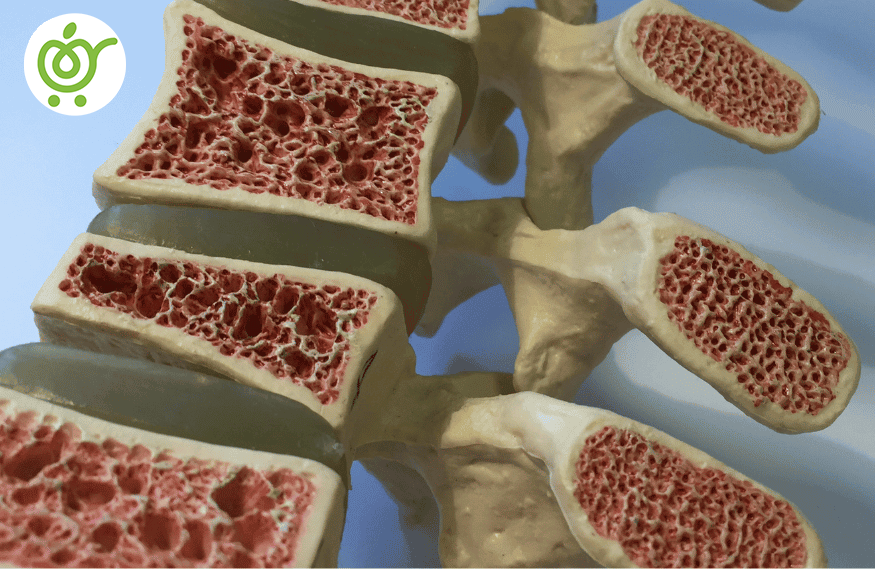

پوکی استخوان

پوکی استخوانی موجب ضعیف شدن بافت استخوان میشود که اشخاص مبتلا را تهدید به شکستگی سریع استخوانها میکند. هر چه میزان پوکی استخوانی بیشتر شود، استخوانها میتوانند به سادگی شکسته شوند؛ به طور مثال حتی با سرفه کردن!

بیشترین بخشهایی که شکستگی آنها را تهدید میکند، لگن، دندهها، مچ دست و ستون فقرات، میباشد. اشخاص ممکن است، بعد از سالها، با شکسته شدن ساده استخوان خود متوجه این عارضه در بدن خود شوند.